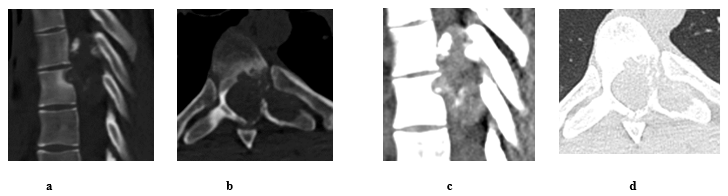

The patient was 19-year-old at time of presentation in early January/2023. He was presented to our spine unit with an incidental finding of T7 lytic lesion with extensive soft tissue involvement (Figure 1 and 2) as seen on CT first, followed by MRI scans. The CT images had been performed as a follow up scans for a previous spontaneous pneumothorax that has been treated for its recurrence with video-assisted thoracoscopic surgery (VATS) combined with left upper lobe apical wedge resection (a bleb inside) and talc pleurodesis in early June/2022. Back then, the x-rays and CT scans for the chest didn’t show a convincing mass lesion (some early lytic changes have been noticed in advance at left T7 pedicle thought to be benign). At presentation, patient had reported 2-week history of back pain and altered sensation from abdomen below with unsteadiness on feet. On exam, patient found to have normal power on limbs, reduced sensation from T7 below and hyperreflexia of knee and ankle. Otherwise, examination was normal. PET scan didn’t show any metastatic lesions.

Figure 1: Pre op spinal CT scan shows a lytic mass lesion on bone window sagittal (a) and axial (b) cuts causes nearby soft tissue and intracanalicular extension with intralesional calcifications as seen on soft tissue window sagittal (c) and axial (d) cuts. It extends behind T6 and T7 with epicentre arising from left body/pedicle of T7. Differential diagnosis based on images Osteoblastoma, Aneurysmal bone cyst and Malignant lesion.